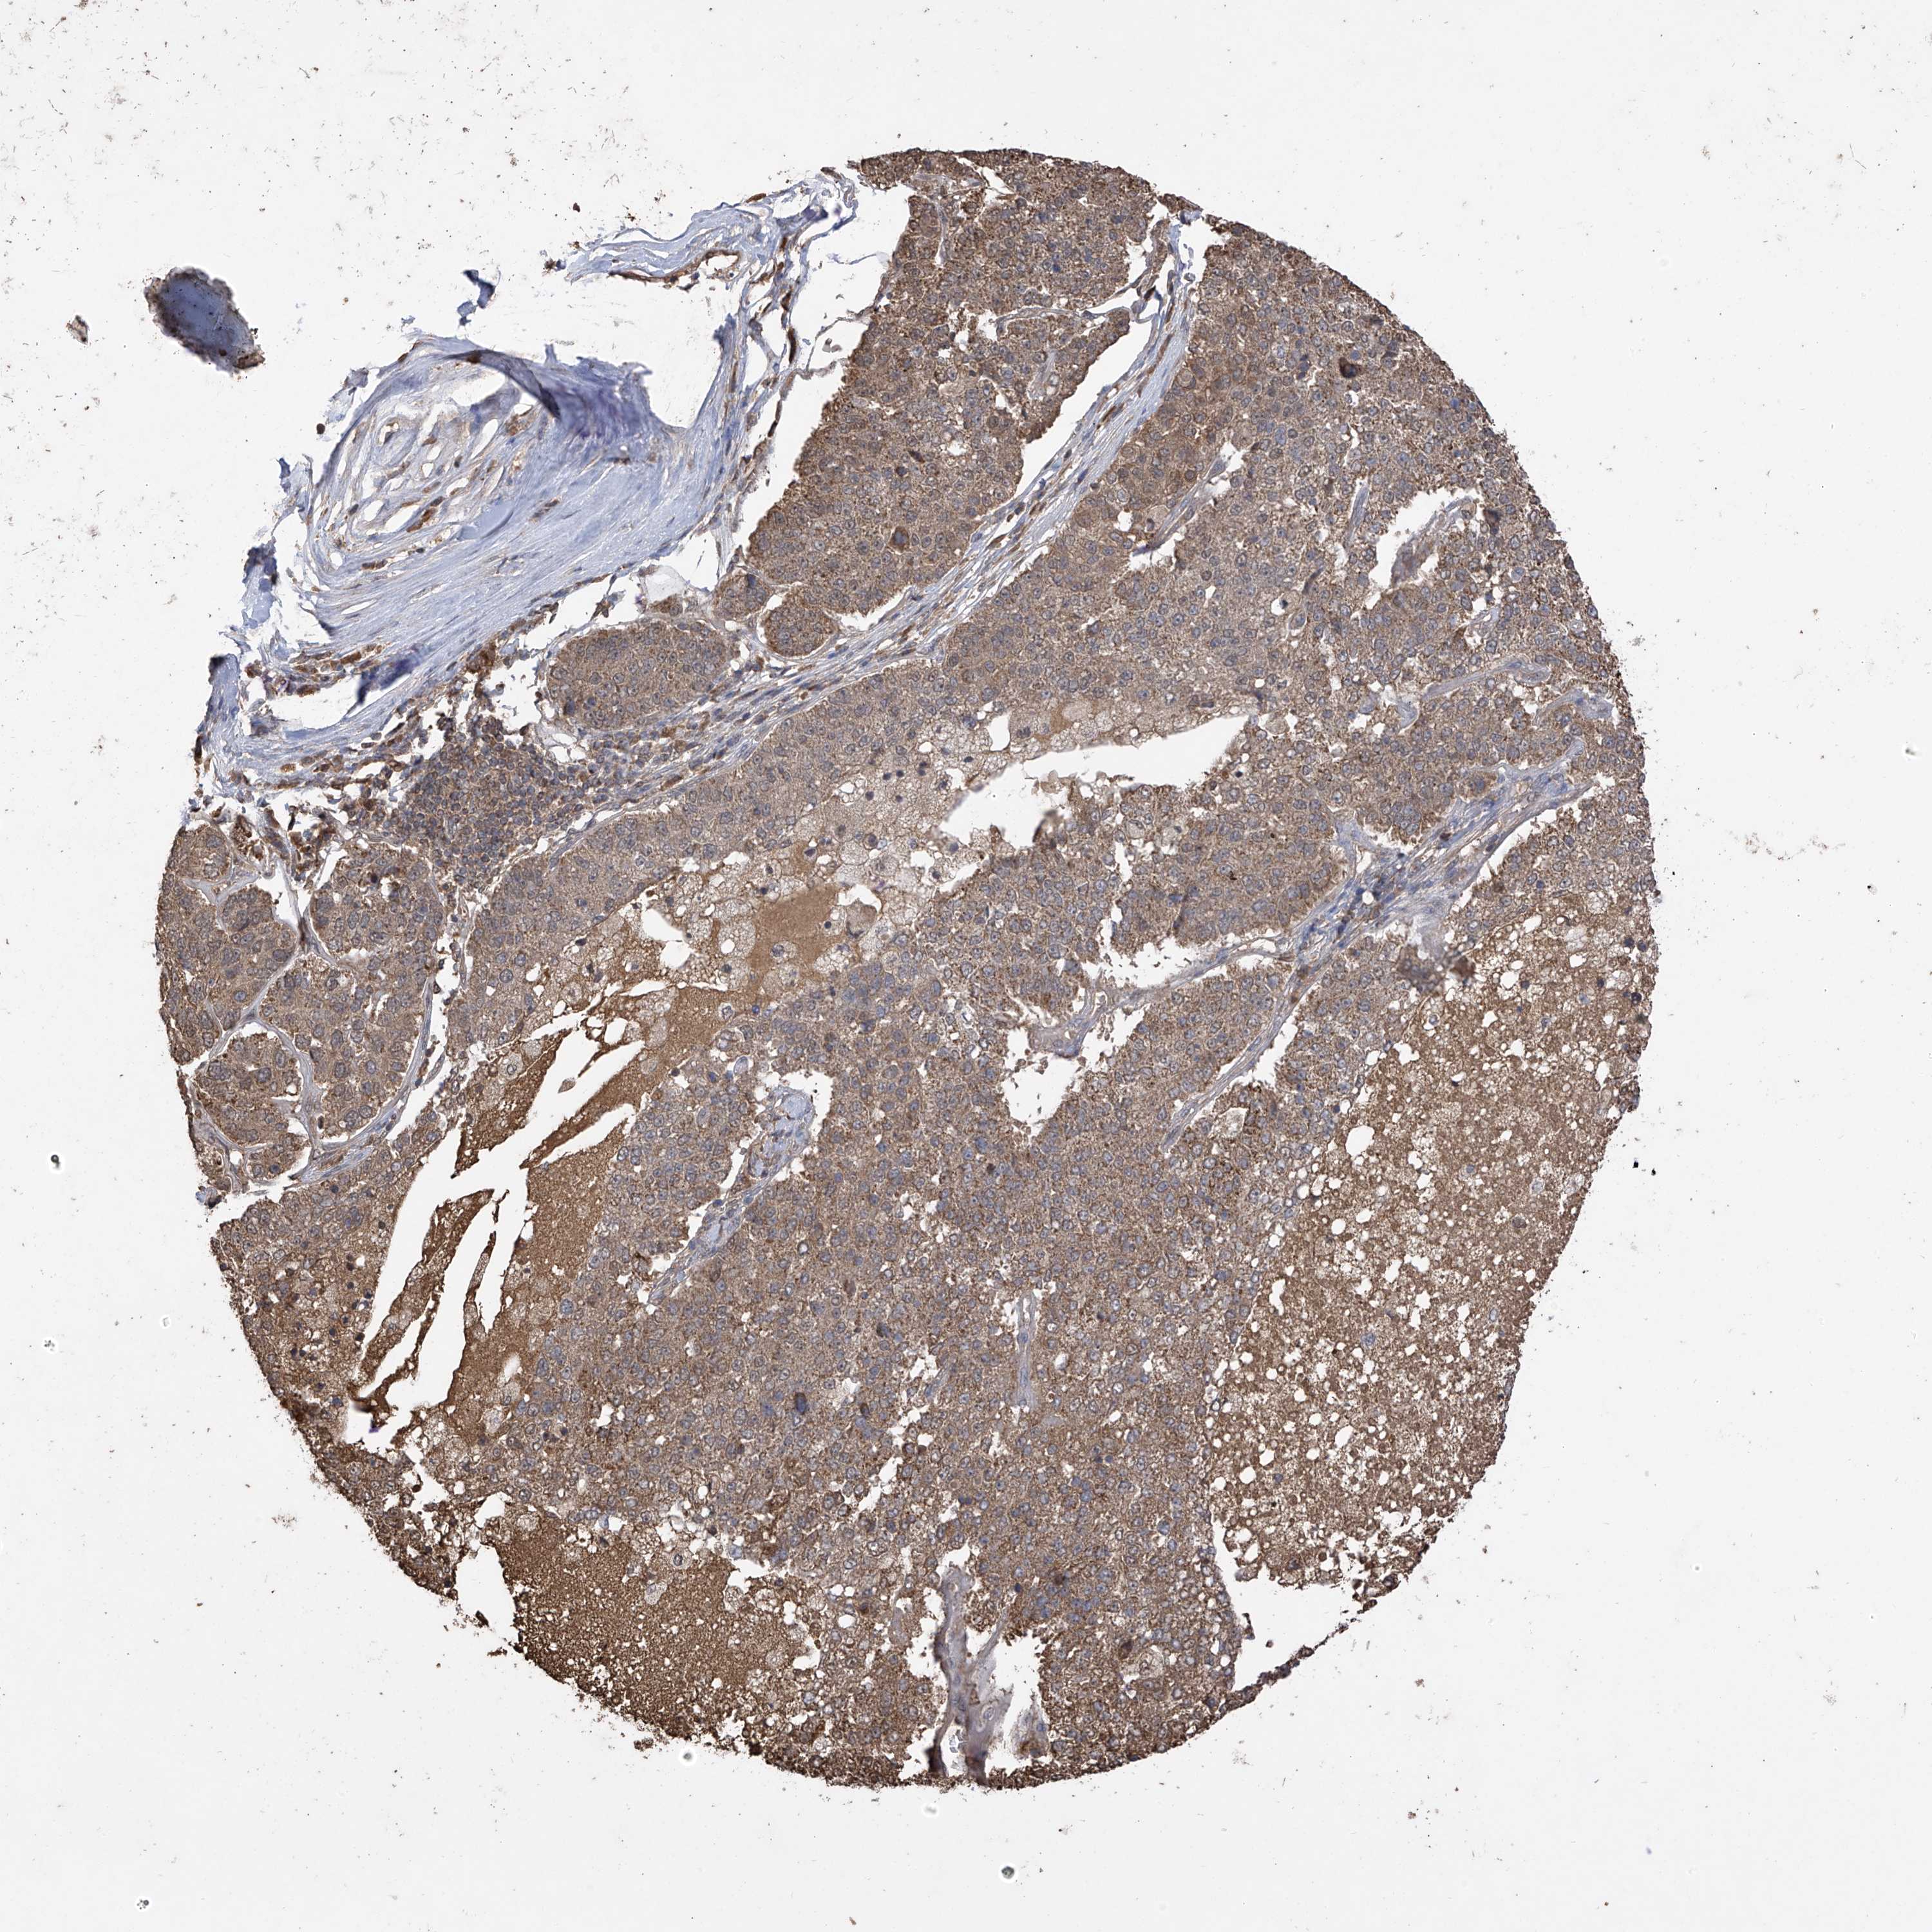

PANCREATIC CANCER - Protein expressioni

A mouse-over function shows sample information and annotation data. Click on an image to view it in a full screen mode. Samples can be filtered based on level of antibody staining by selecting one or several of the following categories: high, medium, low and not detected. The assay and annotation is described here.

Note that samples used for immunohistochemistry by the Human Protein Atlas do not correspond to samples in the TCGA dataset.

Antibody stainingi

Antibody staining in the annotated cell types in the current human tissue is reported as not detected, low, medium, or high, based on conventional immunohistochemistry profiling in selected tissues. This score is based on the combination of the staining intensity and fraction of stained cells.

Each image is clickable and will lead to virtual microscopy that enables deeper exploration of all samples and also displays staining intensity scores, fraction scores and subcellular localization as well as patient and tissue information for each sample.

Antibody HPA034602

Antibody HPA034603

Antibody CAB033424

Staining

High

Medium

Low

Not detected

Intensity

Strong

Moderate

Weak

Negative

Quantity

>75%

75%-25%

<25%

None

Location

Nuclear

Cytoplasmic/membranous

Cytoplasmic/membranous,nuclear

Adenocarcinoma, NOS